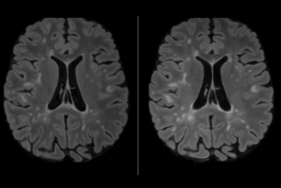

« Concrètement, l’outil issu de ce programme permettra au neurologue de visualiser les évolutions de la maladie à partir de populations SEP ayant les mêmes caractéristiques cliniques et IRM que le patient pris en charge, mais ayant bénéficié de différents traitements, afin de choisir le plus adapté. » Pr Gilles Edan, Service de neurologie du CHU de Rennes, équipe Empenn, CIC Inserm 1414